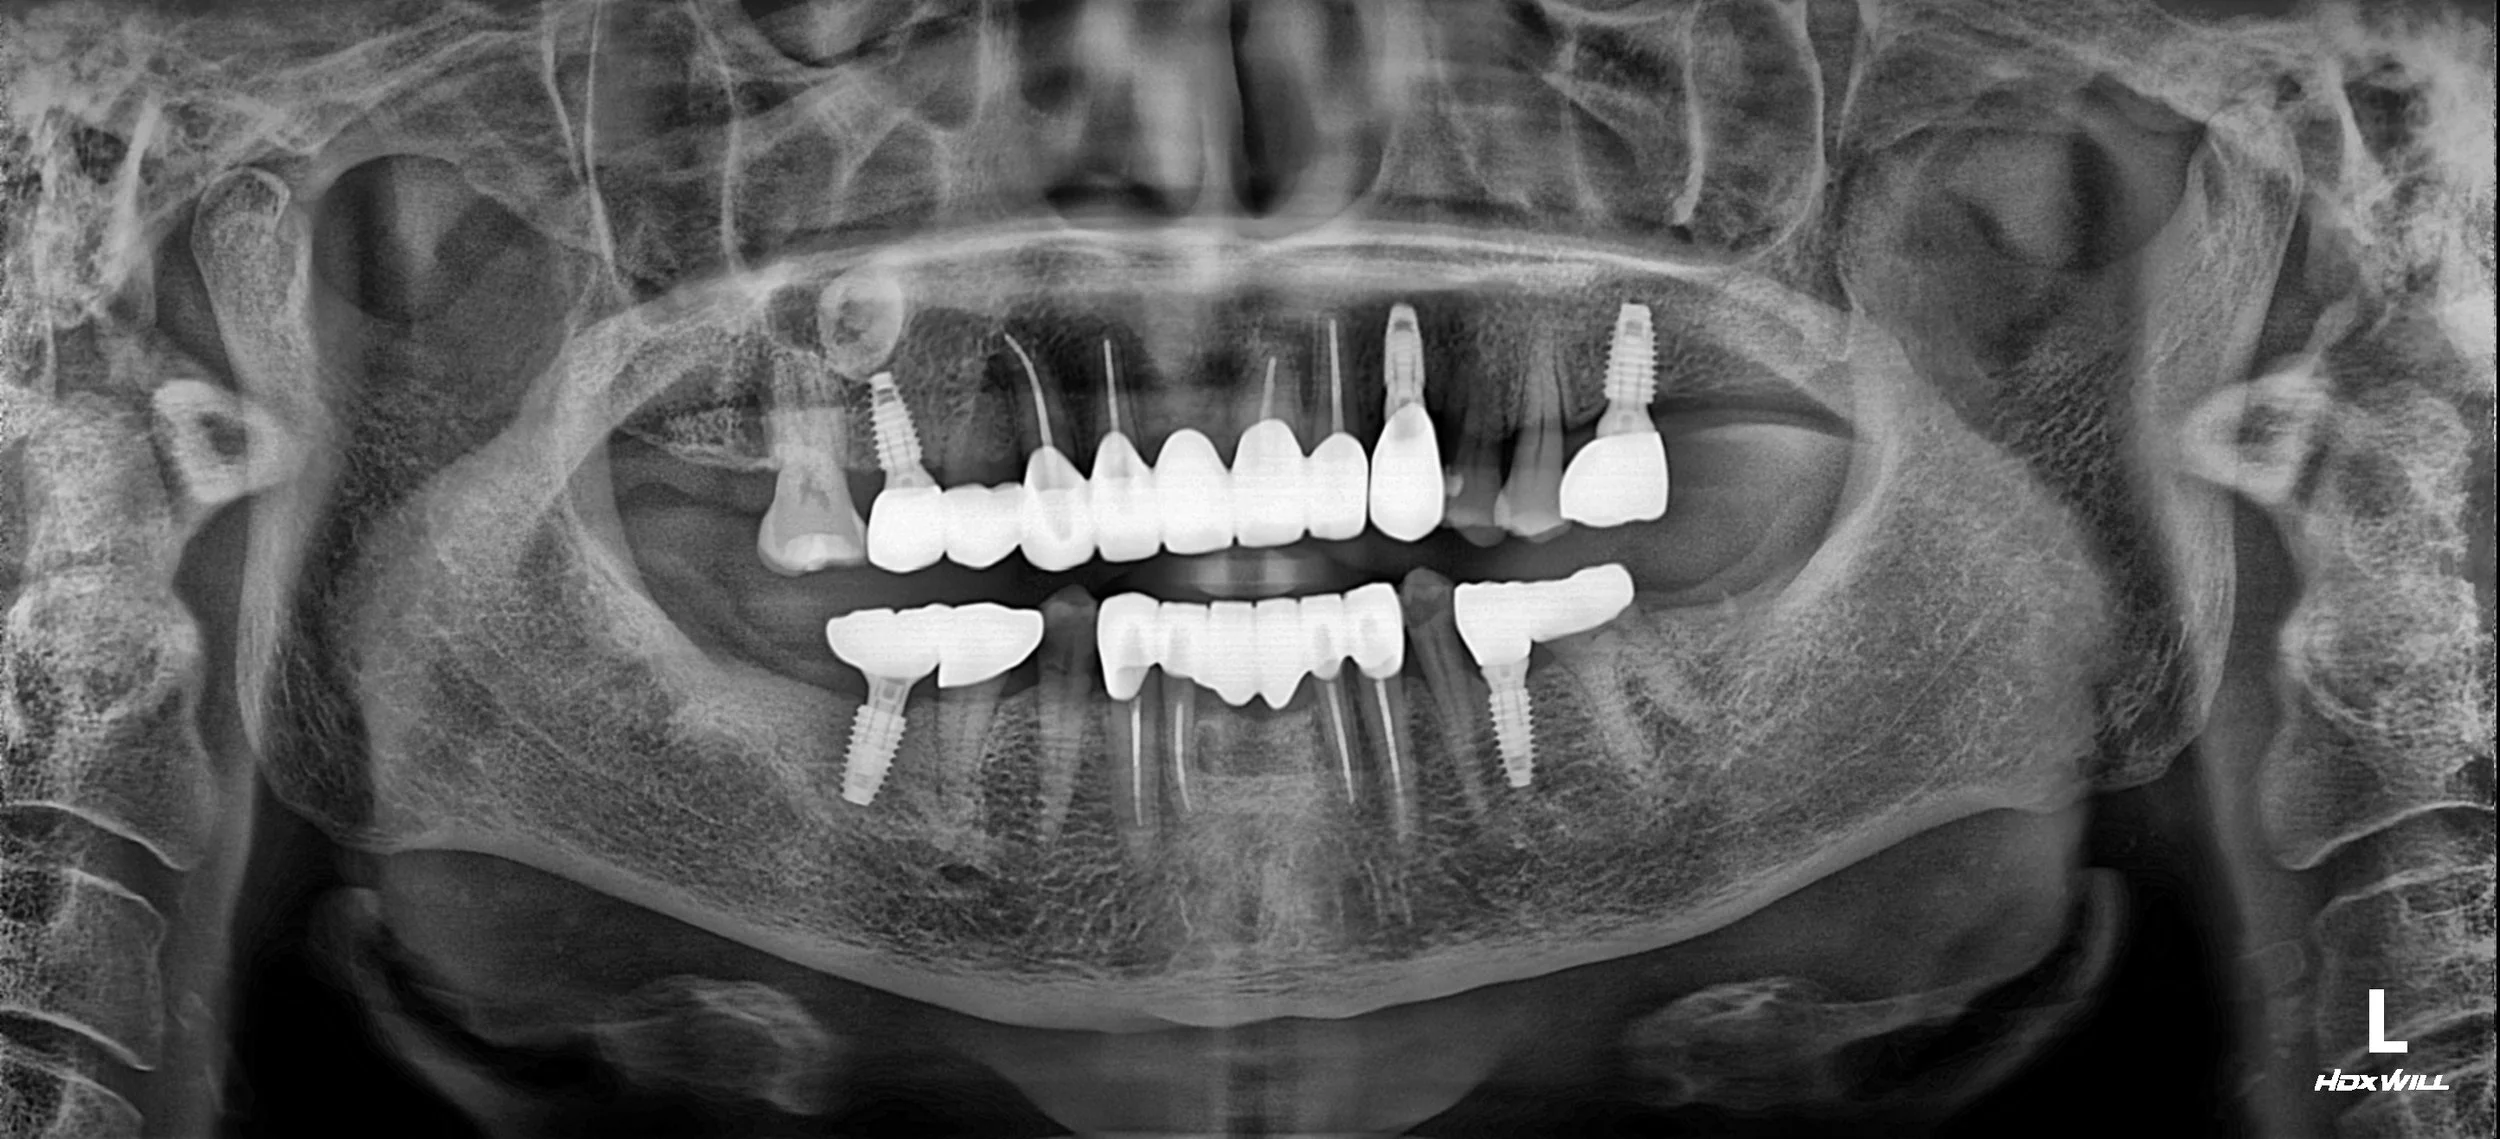

A phased treatment plan was developed and executed. Initially, comprehensive periodontal therapy was performed to stabilize the foundation, along with the removal of hopeless teeth and caries control on salvageable teeth.

Following initial stabilization, a combination of implant-supported and tooth-supported fixed prostheses was planned. Strategic implants were placed in the posterior segments of both arches to provide posterior support. Remaining natural teeth were prepared to serve as abutments for crowns and bridges.

A key aspect of this case was establishing a new, functional vertical dimension of occlusion. The final prostheses were fabricated to provide stable posterior occlusion on the premolars and first molars. Although the second molars were omitted due to cost considerations, this arrangement successfully achieved a stable posterior stop, fulfilling the patient's functional requirements and providing a satisfactory esthetic outcome.